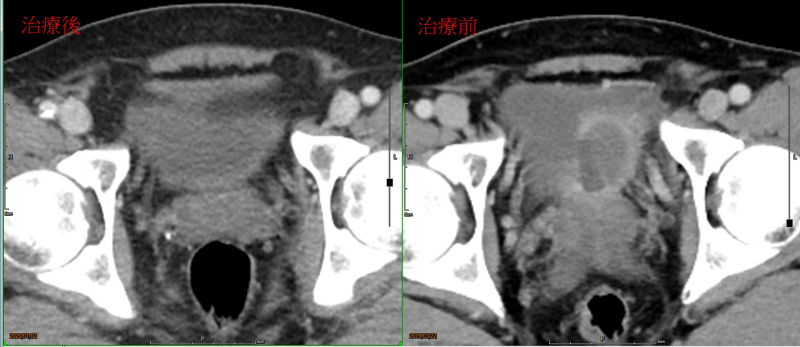

W先生于108年在高雄某大医院确诊膀胱癌cT4aN0M0,并于同年三月开始陆续接受膀胱肿瘤刮除手术及四次全身静脉化学药物合并免疫标靶治疗( Cisplatin, Gemzar and Durvalumab)后。经过核磁共振检查后,医师告知肿瘤大小无明显改变并已有明显的肾脏输尿管水肿无法以双J导管来改善症状,所以医师建议病人膀胱全摘除手术并人工膀胱造口,当下患者及家属是非常无法接受此结果的。经由朋友介绍来咨询本诊所,医师评估肿瘤仅局限原发部位及尚未全身转移之膀胱癌,建议病人接受局部动脉化学药物治疗。此治疗是藉由埋设动脉导管,将化疗药物直接送至供应肿瘤血流之动脉,到达并集中于肿瘤部位,治疗效果特别显著,也能减少其他重要器官曝露在化疗药物的机会,当然产生的副作用也比全身性静脉化学治疗来的轻微。

病人经思考后拒绝接受原本的手术建议,改采取本诊所医师建议的局部动脉化疗治疗。在3个月经过治疗六次动脉化疗后,复检核磁共振指出原部位膀胱肿瘤消失、膀胱镜也无任何异样。